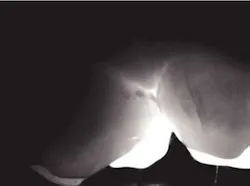

Accurate diagnosis of occlusal caries is problematic at best. Prior to fluoride, the explorer could be retained in an occlusal fissure by factors other than decay. Brown in The Journal of Dental Education (1993) had concerns relative to the reliability and validity of making a diagnosis of occlusal decay based on the retention of an explorer in an occlusal fissure.

By the time there is radiographic evidence of decay, much of the occlusal enamel is undermined. Occlusal decay in patients who have used fluoride in the early years of life has a different anatomical model. The fissures are not open, thus do not give easy access to the dental explorer. The carious lesion starts at the base of the fissure and spreads within the tooth. DIFOTI is particularly efficient in diagnosing this type of decay.

null

Many may say the above DIFOTI image (Fig. 2) only demonstrates stained fissures. The explorer would not enter the fissures at all. The DIFOTI diagnosis was confirmed with a Diagnodent reading in excess of 70. The tooth was restored in a minimally invasive fashion.